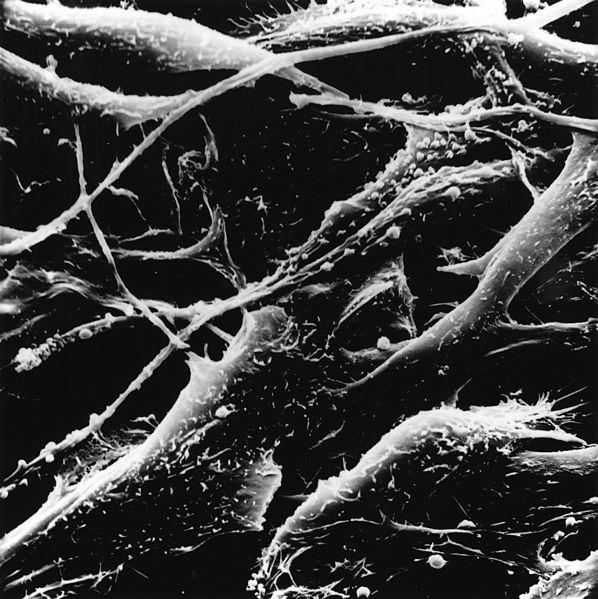

When fecal transplants from cancer patients who were not resistance to PD-1 blockade were given to antibiotic treated mice, the efficacy of the anti-PD-1 treatment increased. Providing probiotics made of Akkermansia muciniphila also helped restore the effect of anti-PD-1 ICI. The mechanism of this was dependent on Il-12 which increased CCR9+CXCR3+CD4+ T lymphocytes.